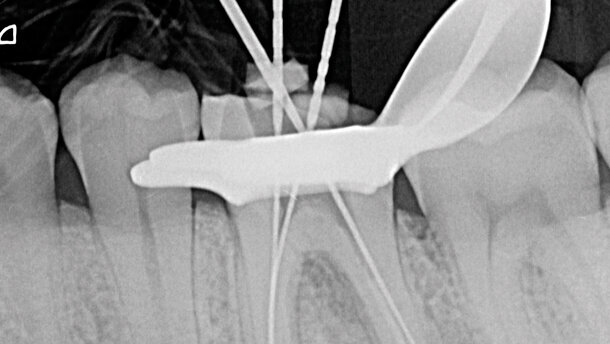

Viene presentato, a titolo esemplificativo, il caso di un primo molare inferiore di sinistra precedentemente “maltrattato” endodonticamente, che presentava una grossa lesione periradicolare a carico della radice distale e una più piccola in corrispondenza dell’apice di quella mesiale (Fig. 3). È stato scelto come strumento per la sagomatura di questo elemento dentario l’F6 SkyTaper “rosso” (Fig. 4). Dopo aver rimosso tutto il vecchio materiale utilizzato per la ricostruzione e aver realizzato una corretta cavità d’accesso (Fig. 5), con un k-file 10 e un k-file 15 tutti i 4 canali radicolari sono stati sondati fino alla lunghezza di lavoro determinata elettronicamente (Fig. 6). È stato realizzato il GlidePath meccanico con il PathGlider portato fino alla lunghezza di lavoro; questo ha creato un canale regolare che ha permesso all’F6 SkyTaper Rosso di poter scivolare fino alla lunghezza di lavoro di tutti e quattro i canali radicolari. Pur trattandosi di un ritrattamento, l’eccellente capacità di taglio dell’F6 SkyTaper ha permesso di rimuovere con efficacia tutto il vecchio materiale infetto che era stato inserito all’interno dei canali radicolari.